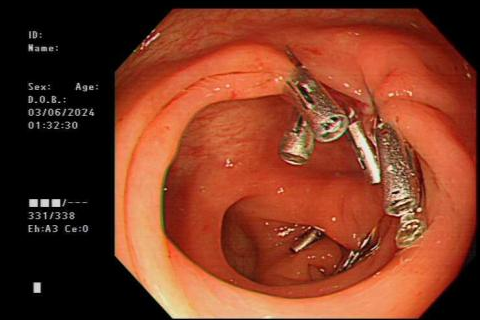

钟XX,男性,40岁,因“黑便、呕血半天”入院。入院完善相关检查后行胃镜检查,发现食管贲门黏膜多处纵行撕裂并活动性出血,其中一处病灶为喷射样出血,需要及时进行止血治疗。消化内科团队迅速为患者进行内镜下止血治疗,对食管贲门黏膜撕裂出血口给予套扎止血,其余撕裂渗血灶给予电凝止血,成功止血后进行下一步对症治疗,目前患者已出院。

内镜下套扎止血